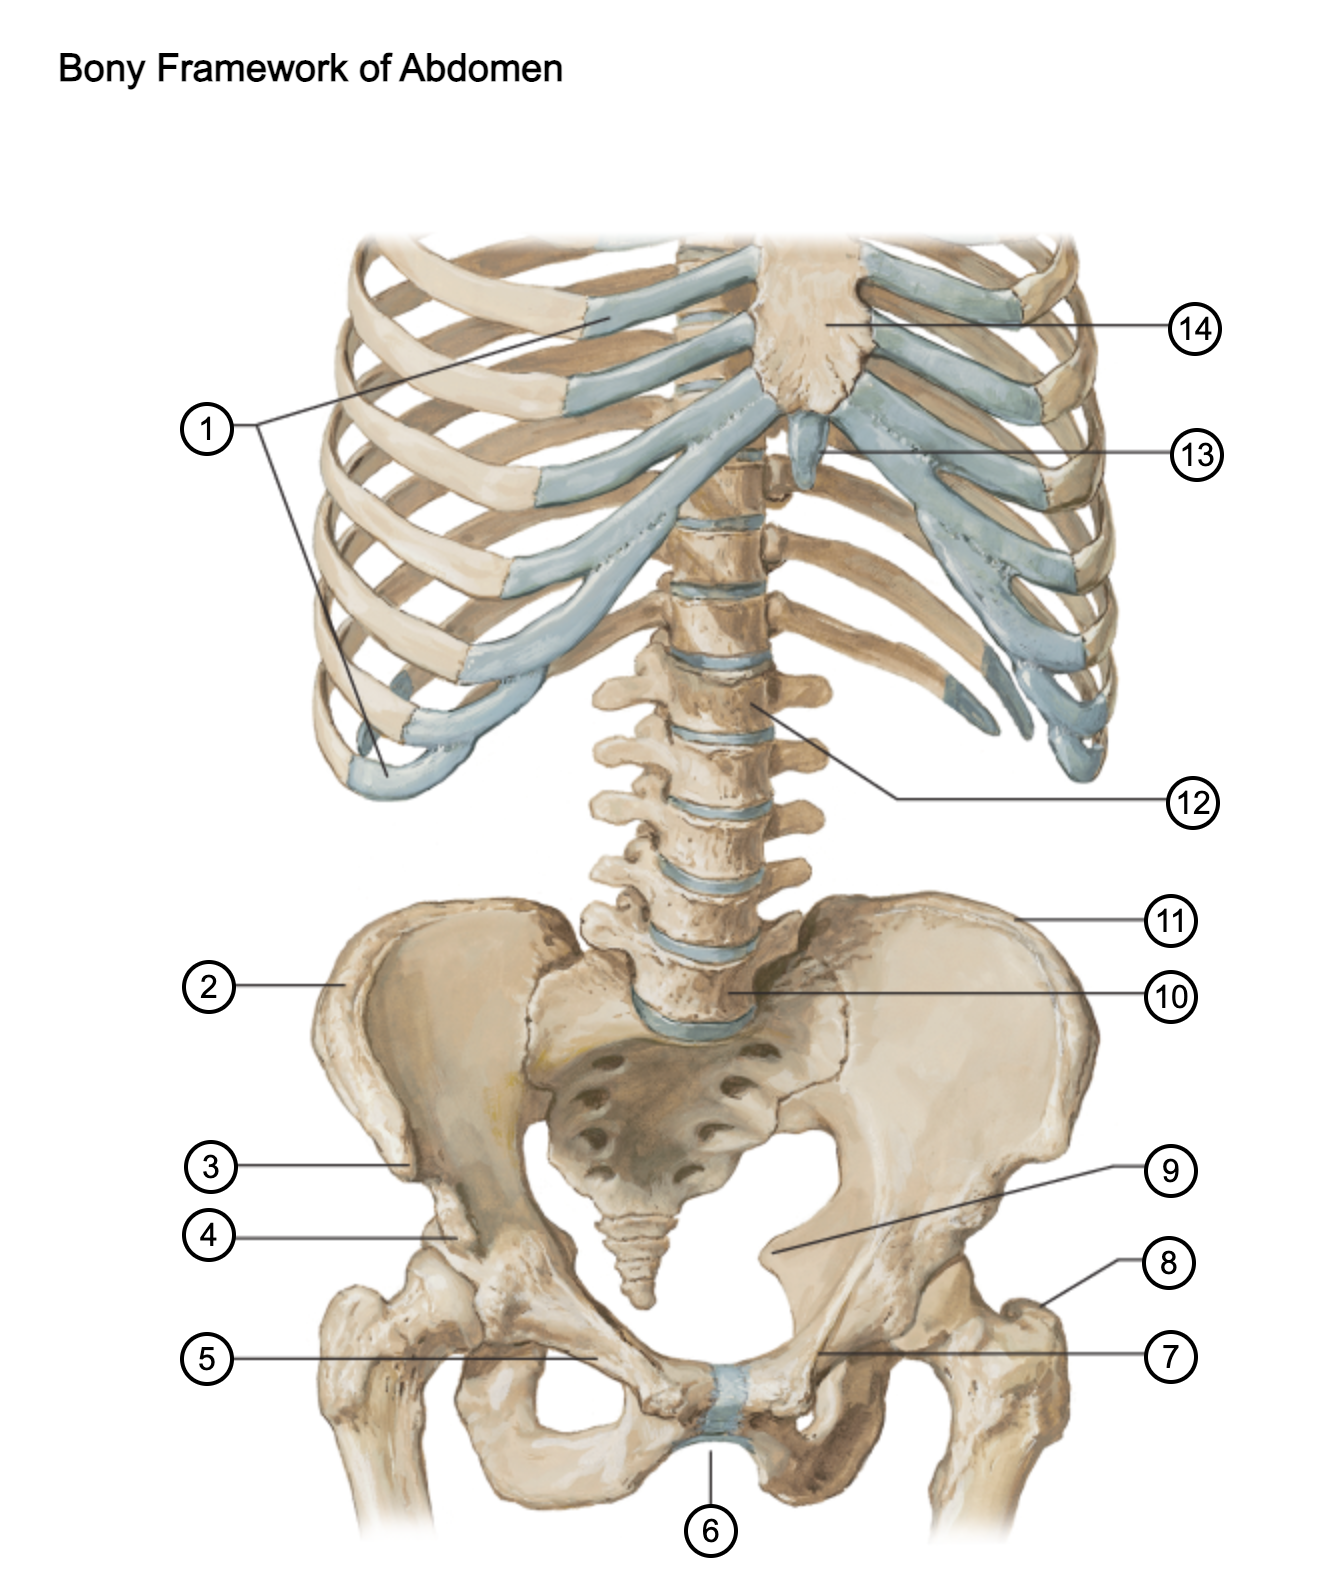

1

costal cartilages

2

iliac crest

3

anterior superior iliac spine

4

anterior inferior iliac spine

5

superior pubic ramus

6

pubic arch

7

pecten pubis

8

greater trochanter

9

ischial spine

10

L5 vertebra

11

iliac crest

12

L1 vertebra

13

xiphoid process

14

body of sternum